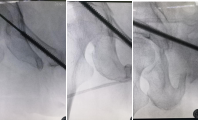

缪博副主任医师带领医疗团队根据李女士的实际情况,结合目前国内的先进的治疗手段,为她量身制定了微创通道螺钉内固定耻骨上支和髋臼前柱骨折的治疗方案。目前,通道螺钉技术是国内刚刚兴起的微创手术技术,它对于手术者的技术要求非常高。手术医生要在患者的直径仅有1~1.5cm的且带有一定弧度和斜度的耻骨上支精准地打入一枚直径为6.5mm,长度为100mm以上的螺钉,稍有不慎就会损伤到耻骨支前方腹股沟韧带内穿行的股血管和股神经,造成不可收拾的结果,而完成这么复杂而精准的手术,仅仅需要在患者耻骨结节下方切一个1cm左右的小切口。目前我省只有几位骨创科专家掌握这项技术,还有几个兄弟医院正在使用手术机器人引导下摸索学习和实践这一新技术。缪博副主任医师和医疗团队的医师们,凭借扎实的微创内固定技术和对骨盆解剖结构的熟练掌握,仅在普通的术中C型臂透视引导下,用时1个小时左右,顺利完成了我院第一例通道螺钉微创内固定骨盆骨折的手术。而且,我院这例手术不但固定了耻骨上支骨折,还固定了髋臼前柱骨折,难度更高,这也是对于通道螺钉技术的一次新的尝试和突破。

李女士在术后第1天就可以坐起进食和饮水,并开始在医师指导下进行腿部功能锻炼,其右侧腹股沟区的疼痛也缓解了,她对这次手术的效果非常满意。经过创伤中心医护团队的精心呵护,悉心指导患者功能锻炼,术后2周,李女士就顺利出院。出院后,李女士在家中继续遵照医师的指导进行功能康复训练,并按照医嘱在出院后1月左右来门诊复查,于是,出现了文章开头的那一幕。现在,李女士对自己的康复和日后的生活更加充满了信心。